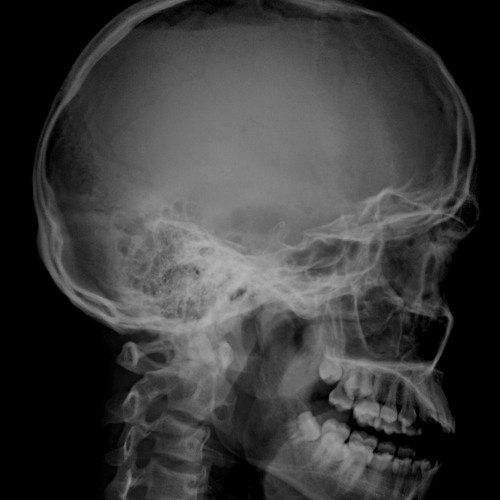

Анатомия мозга: Рентгеновские снимки для презентаций